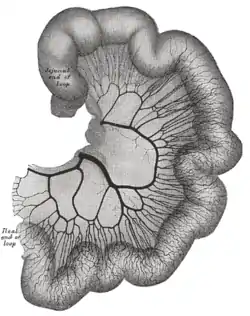

Loop of small intestine showing distribution of intestinal arteries | |

The arterial arcades (intermesenteric arterial anastomoses or Riolan arcades[1]) are a series of anastomosing arterial arches between the arterial branches of the jejunum and ileum.

Nearest the duodenum the mesenteric loops are primary, the vasa recta are long and regular in distribution, and the translucent spaces (lunettes) are extensive.

Toward the ileocolic junction, secondary and tertiary loops are observed, the vessels are smaller and become obscured by numerous fat-tabs.

The diagrams below show the arrangement and variations of the loops of the mesenteric vessels for various segments of the small intestine of average length: